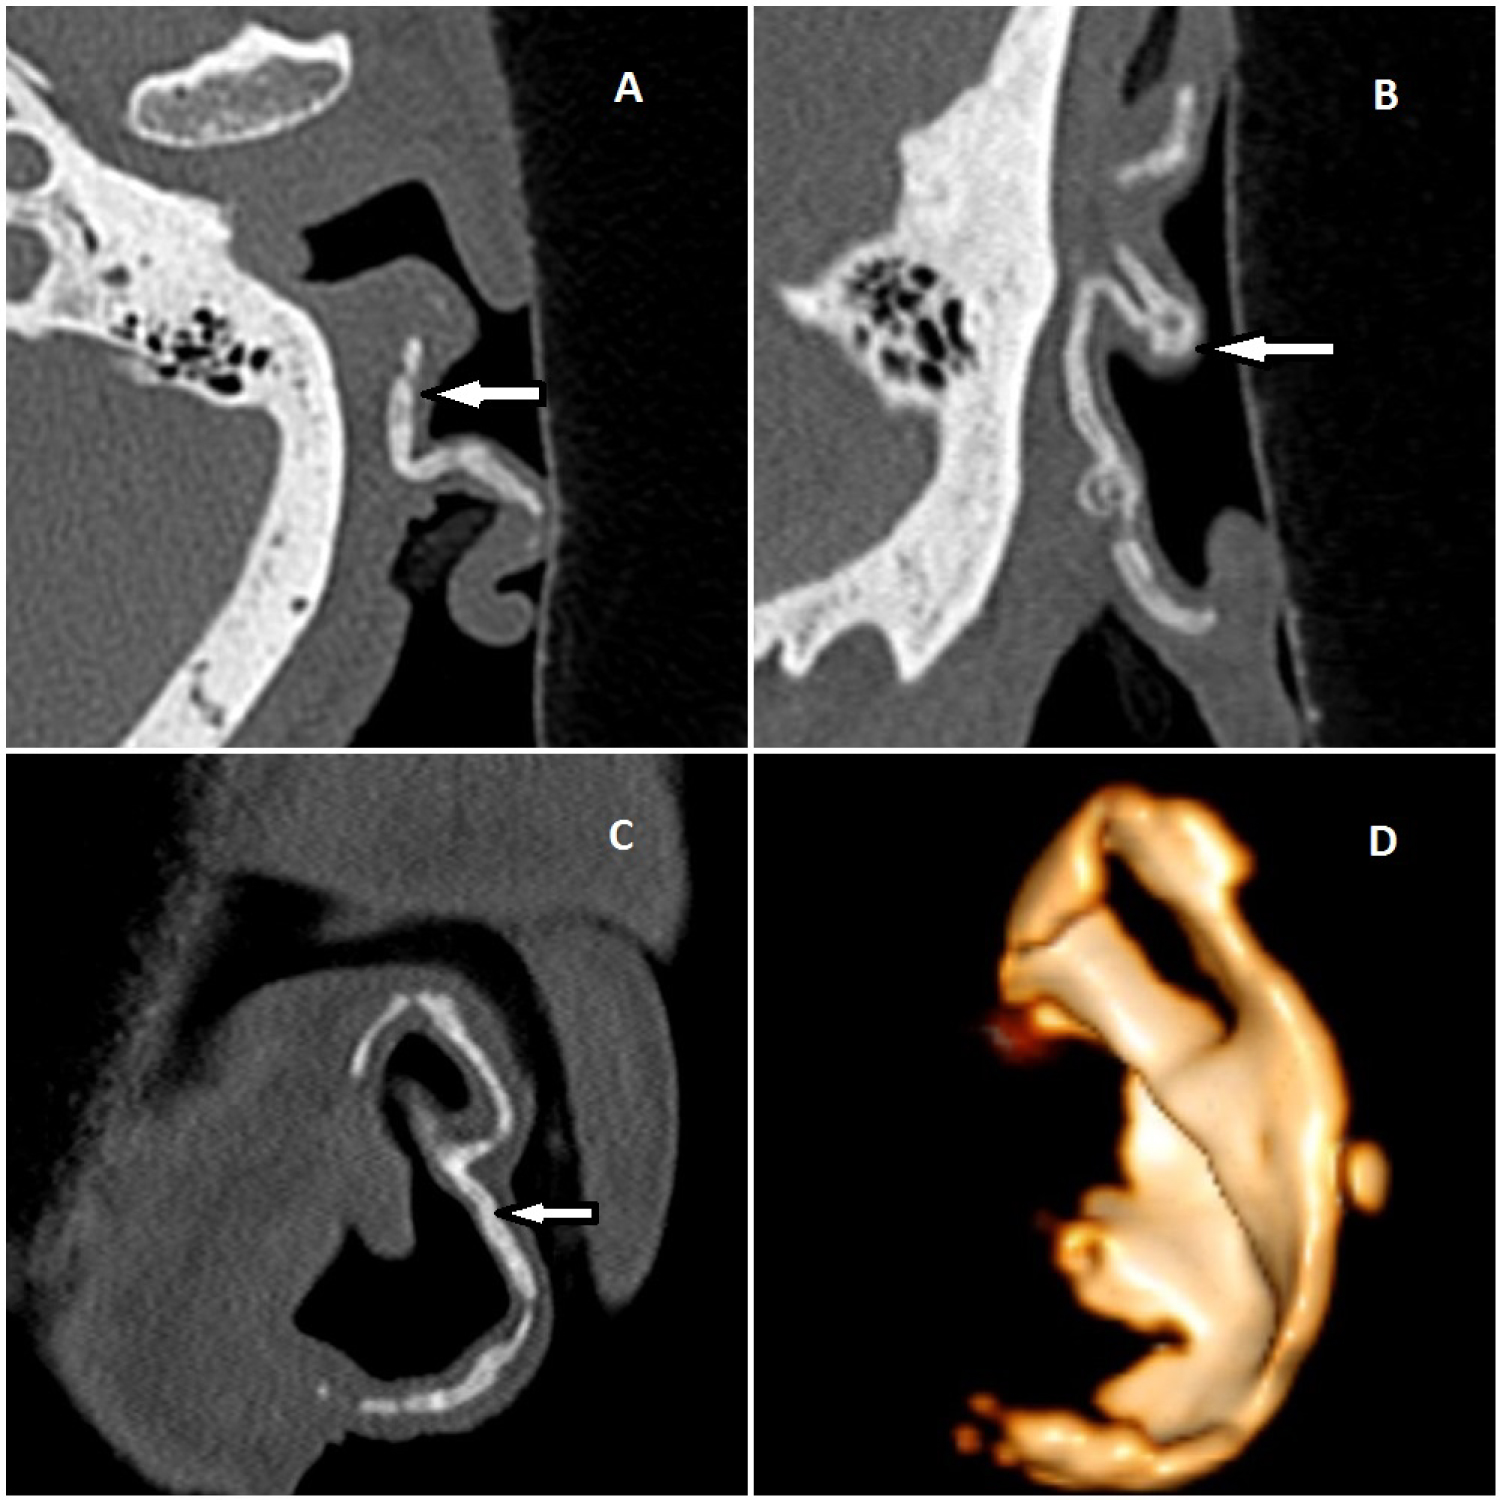

Calcification or ossification of the left external auricular cartilage was demonstrated on non-contrast temporal bone Computed Tomography (CT) scan (Figure 1A-Axial, Figure 1B-Sagital, Figure 1C-Coronal image). Volume Rendered Technique (VRT) shows three dimensional images of calcified auricular cartilage (Figure 1D). Based on above clinical and radiographic findings, a rare diagnosis of idiopathic petrified left ear was made.

Figure 1: (A) Axial; (B) Sagital and; (C) Coronal reformated images on non-contrast temporal bone Computed Tomography (CT) scan demonstrated calcification or ossification of the left external auricular cartilage. Volume rendered technique; (D) Reveals three dimensional images of calcified auricular cartilage.